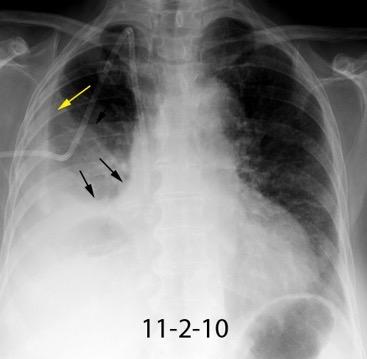

Visible en radiografías en decúbito supino de los pacientes con neumotórax por la acumulación de aire en el seno costofrénico.

“Deep sulcus sign”. Seno costofrénico aumentado en anchura y profundidad

Polireddy K et al. Blunt thoracic trauma: role of chest radiography and comparison with CT findings and literature review . Emerg Radiol 2022.

Kumaresh A et al. Back to Basics – ‘Must Know’ Classical Signs in Thoracic Radiology. Thoracic Radiology. J Clin Imaging Sci 2015.